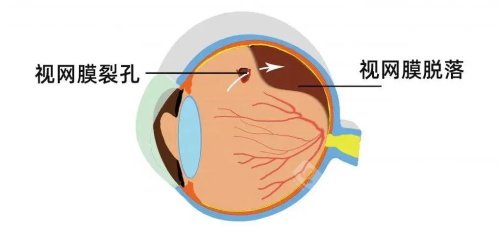

孙医生在玻璃体视网膜手术方面具有独特技术优势,采用国内外靠前的小创口玻璃体切割技术治疗复杂性视网膜脱离,手术成功几率达90%以上。

在高度近视并发症治疗方面,孙医生采用个性化方案,针对黄斑裂孔、视网膜劈裂等病变开展精密手术干预。